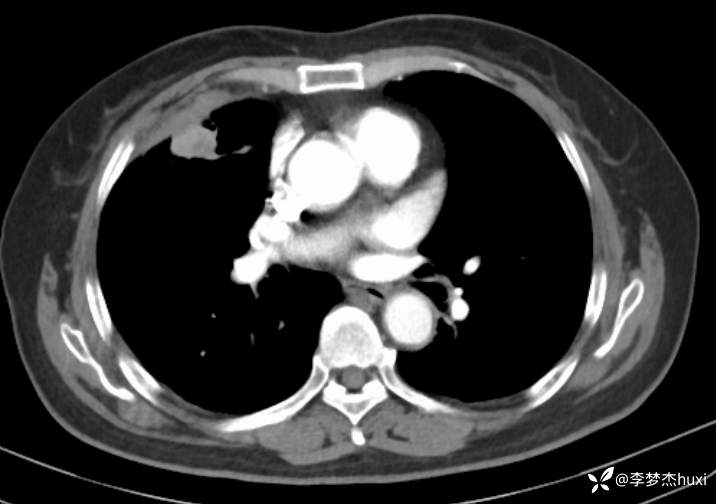

辅助检查:胸部CT:右肺占位?炎症?双肺炎性变,左肺下叶陈旧性病变,双肺纹理增多,主动脉及冠状动脉钙化,双侧胸膜局部增厚,胆囊结石,多发肝囊肿?请结合超声。

临床诊断:肺占位